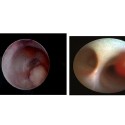

Γαλακτοσκόπηση εργαλεία

Τεχνική γαλακτοσκόπησης

Γαλακτοσκόπιο και Mammary pump

Εικόνες γαλακτοσκόπησης

Εικόνες γαλακτοσκόπησης